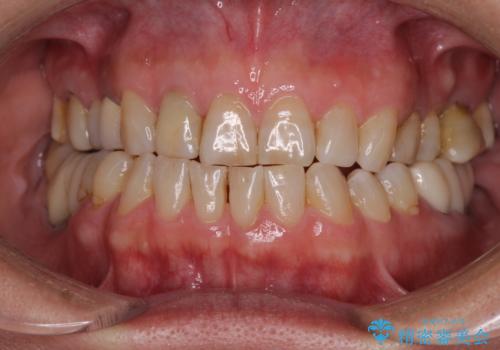

憧れの白い歯に 全顎セラミック治療

- 60歳を越え、黄ばんだ前歯をセラミッククラウンできれいな口元にしたいとのことで来院された患者様です。

診察したところ、前歯は反対咬合であり、その影響で抜歯が必要な奥歯があることが分かりました。

抜歯が必要な奥歯は、インプラント並びにブリッジにより補綴を行い、上下前歯は反対咬合を改善させるように補綴治療を行うこととしました。

健全な歯を削ってセラミッククラウンに置き換えることは、本来避けるべき治療と考えますが、今回は①患者様が60歳を越えていること、②要改善の咬合により抜歯が必要な奥歯があること、③反対咬合の前歯改善の手段としてセラミック治療が選択肢にあることなどから、全顎的なセラミック治療を行うこととしました。